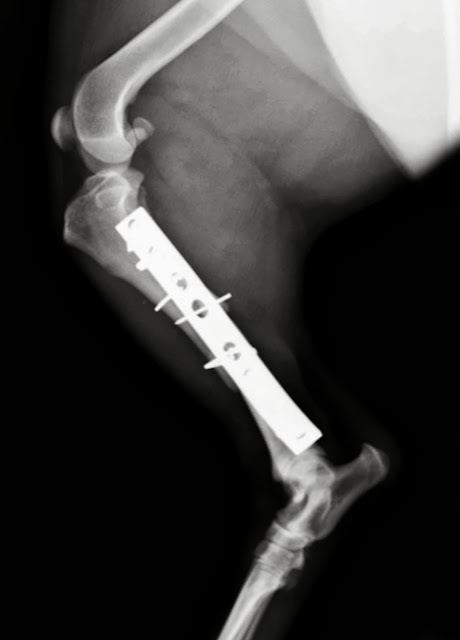

Tras la

cirugía, haremos las correspondientes radiografías de control, que expongo a

continuación, en primer lugar la vista medio lateral:

Y esta

sería la imagen post operatoria que se corresponde con la vista radiográfica antero posterior del mismo paciente:

Comprobamos

que la reducción de las fracturas es buena, la articulación tiene congruencia,

los implantes proporcionan una estabilidad suficiente, y si se logra un adecuado

control de la actividad del paciente, la evolución debería ser favorable.